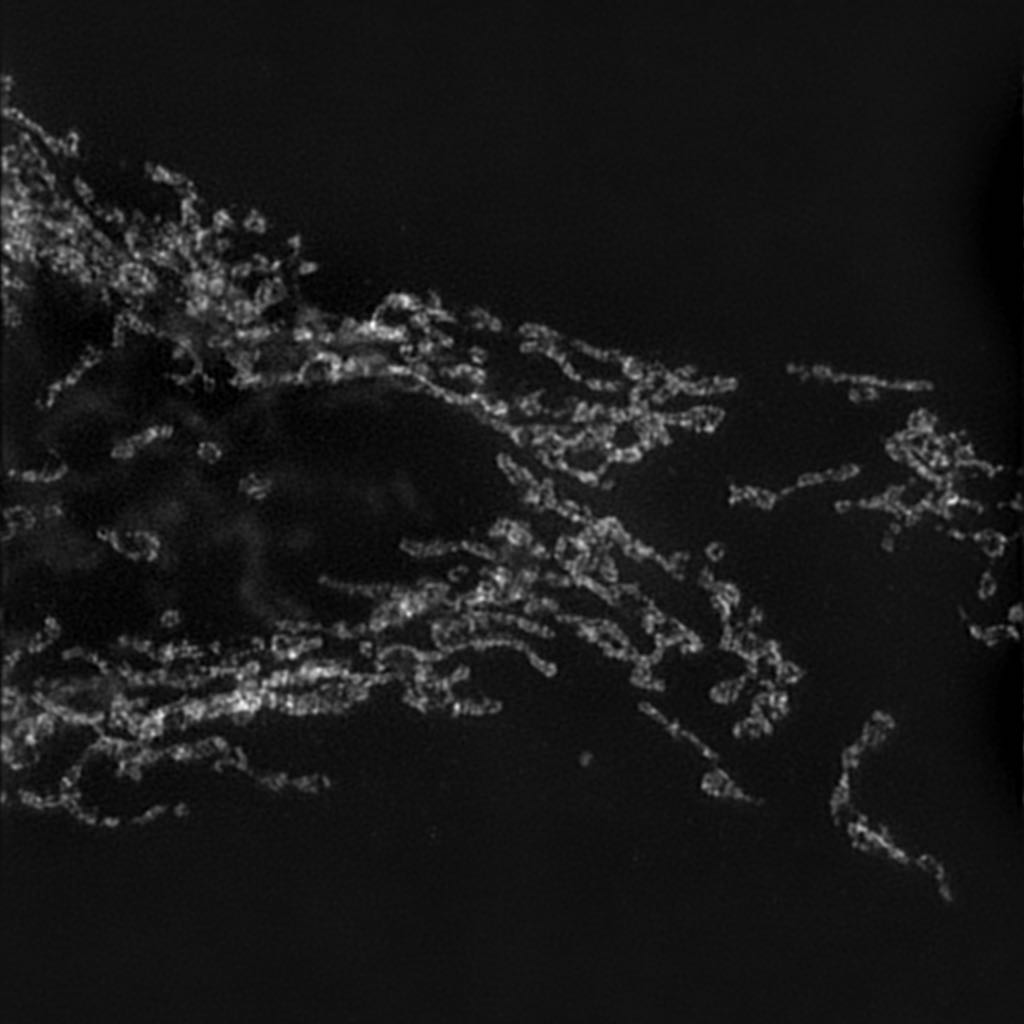

For that purpose, we use the Widefield to SIM (W2S) [13] dataset which consists of grayscale image acquisitions of human cell samples with different fields of view and acquisition wavelengths, before any processing and after the SIM process. This will allow the network to automatically recover a high-definition and denoised version of the image as if it were acquired with SIM. In this dataset, the images size is 512 ×\times 512 pixels in low resolution and 1024 ×\times 1024 in high resolution. The SIM process produced images of twice the resolution of the first image.

Refer to caption

Low resolution (input)

High resolution (target)

Figure 1: Image pair from W2S [13]. The low resolution image has half the size of the high resolution one. For better visualisation, it is upsampled by a factor 2 using bicubic interpolation